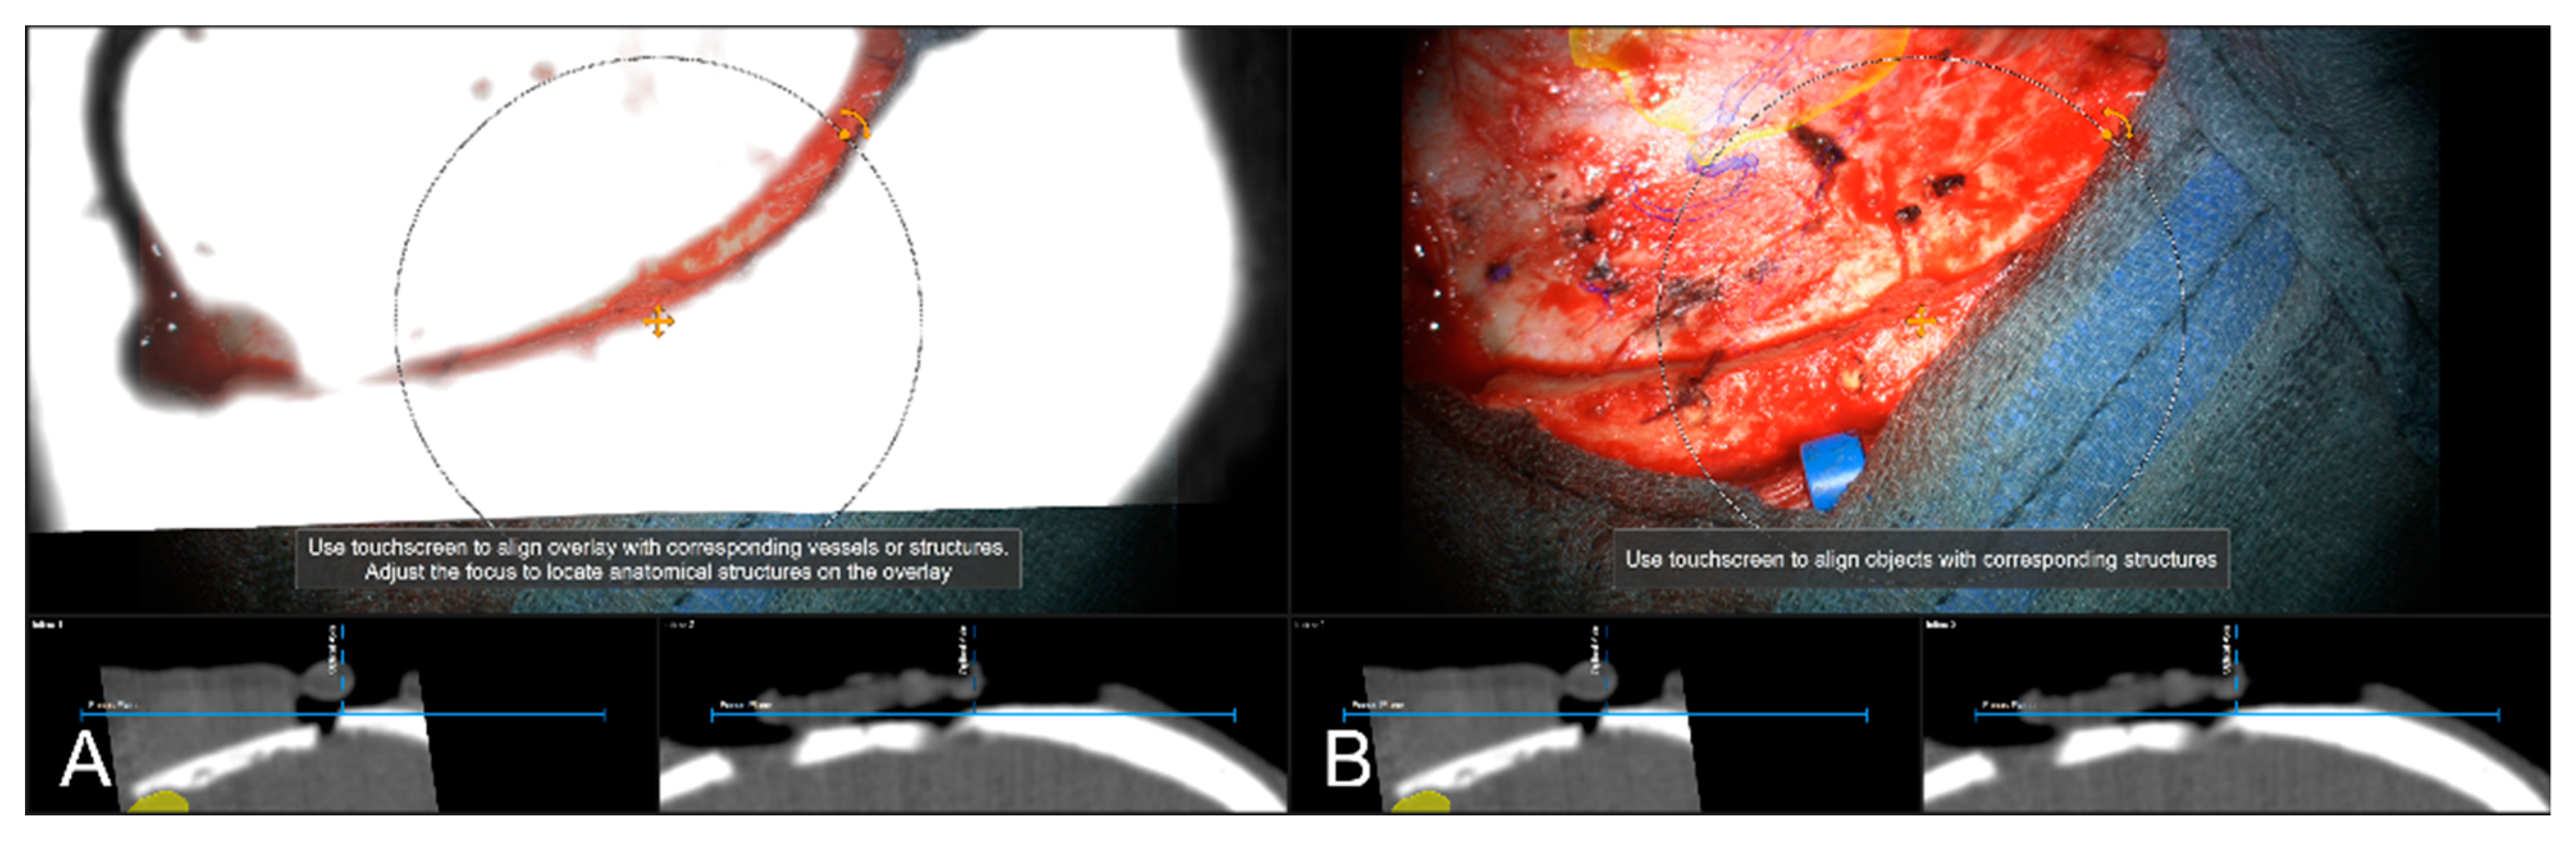

Figure 5. Using an intraoperatively conducted CT scan for automatic patient registration after craniotomy for evaluation of navigation accuracy showing a sufficient in-plane match of MIP (A) and patient anatomy (B). (In parallel view of MIP projection and patient anatomy (upper part) and inline views with the recent focus plane (blue line) and the optical axis (dashed blue line) in the bottom part).

Sensors 22 09591 g005

Figure 6. Navigation inaccuracy seen in the recent focus plane utilizing a MIP of the intraoperative automatic registration CT image set acquired after craniotomy showing the translational mismatch of MIP and patient anatomy (A) and the match of MIP and patients anatomy in the recent focus plane after manual correction (translation) of the visual misalignment (B). (In parallel view of MIP projection (upper part) and inline views with the recent focus plane (blue line) and the optical axis (dashed blue line) in the bottom part).

Sensors 22 09591 g006

In 85 cases (29.01%), a pre-resectional CT data set (preoperative routine CT data or intraoperative CT conducted for automatic registration) was used to examine navigation accuracy using bony landmarks, such as burr-holes (one case, prior biopsy) and edges of craniotomy itself. In 83 cases (97.65%) out of those cases, navigation accuracy was evaluated to be sufficient, see Figure 5. In two cases (2.35%), there was a need for updating the used registration to account for the obvious in-plane mismatch of MIP and patient anatomy by rigidly translating the image data within the recent focus plane, see Figure 6. In both cases, the misalignment was compensated for by translating the projected data by means of 6.27 ± 7.31 mm.